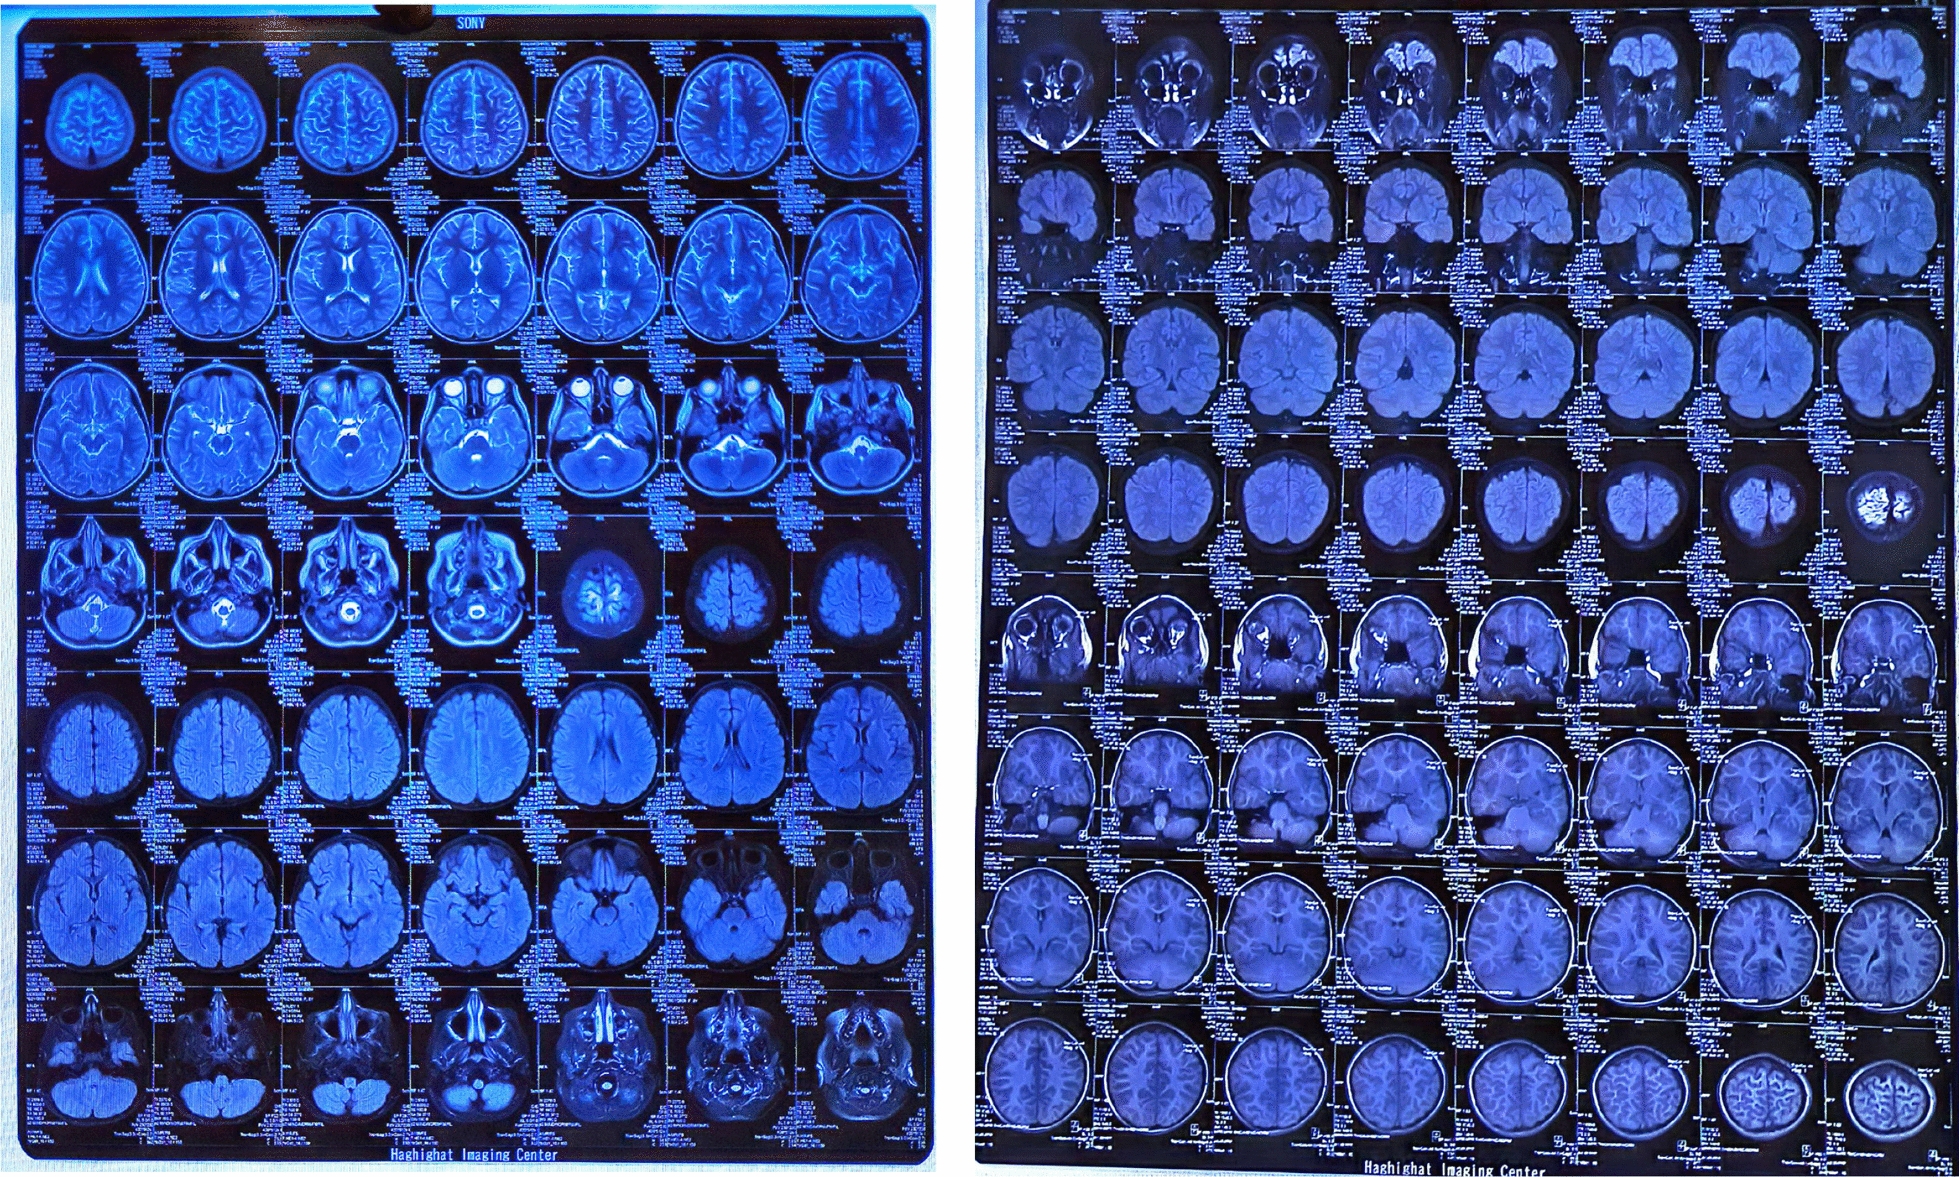

Diagnostic medical imaging

To examine the patient more closely, computed tomography (CT) scan and magnetic resonance imaging (MRI) of the brain; chest X-ray (CXR); ultrasound of the thyroid, abdomen, and pelvis; and electroencephalogram (EEG) tests were requested and performed.

In thyroid ultrasound, both thyroid lobes were normal with homogeneous parenchymal echo and without solid-cystic lesions, and no abnormal findings were seen. In the uterus and ovary ultrasound, the uterus and ovaries had normal echo and dimensions, and there was no evidence of cystic or solid lesions.

The MRI findings were normal, but several diffuse cortical hyperintensities were observed, consistent with the patient’s history of anti-NMDAR encephalitis. This may indicate an inflammatory process related to a relapse. However, the overall normal findings and the absence of abnormalities in complementary imaging studies, including brain CT, chest X-ray, and ultrasounds, suggest no concurrent structural or systemic pathology. The EEG was also evaluated and found normal (Figs. 1, 2, 3).